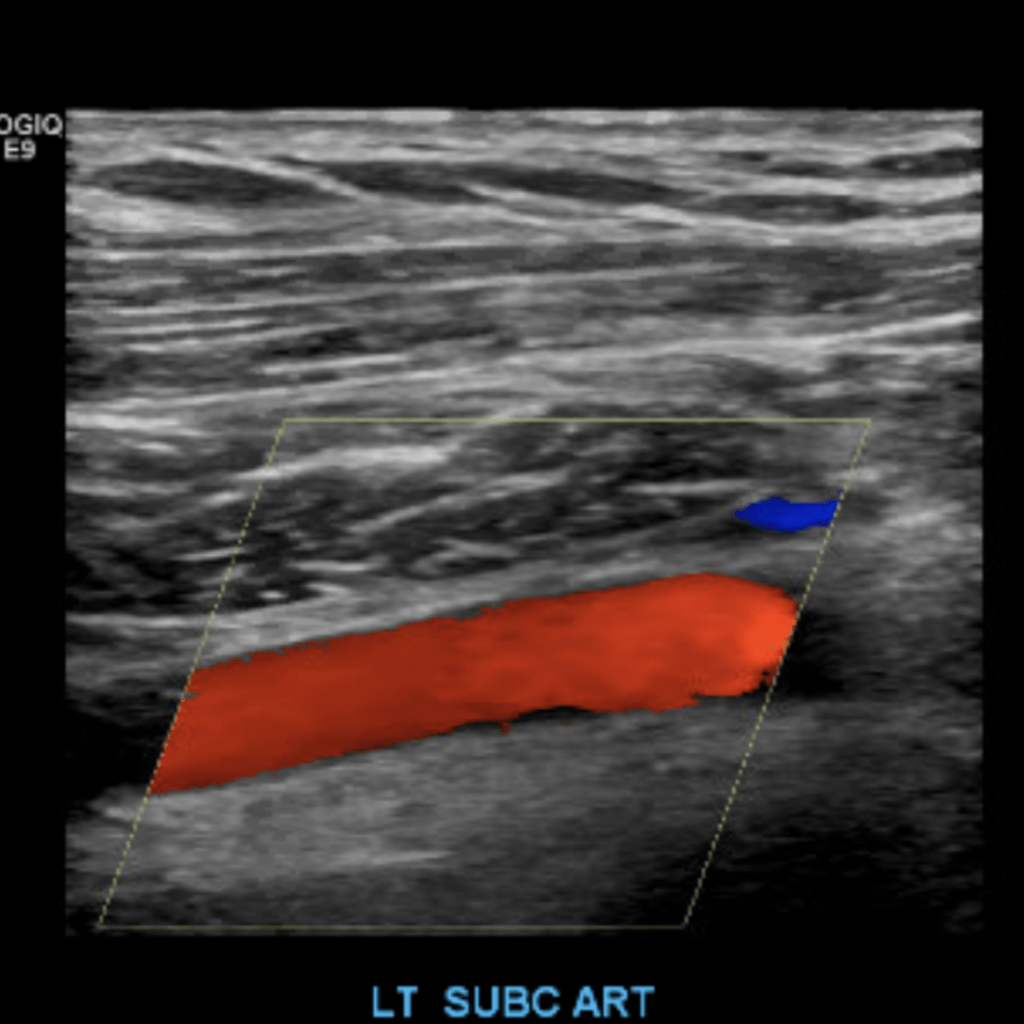

Duplex sonography of the extremities is a non-invasive and valuable tool in detecting diseases in the blood vessels of the arms and legs. This post will cover the basic evaluation of the upper and lower extremity arterial systems.

The subclavian artery arises from the brachiocephalic artery on the right and off of the aortic arch on the left. This artery further divides into the axillary, brachial, radial, ulnar, palmar and digital arteries respectively.